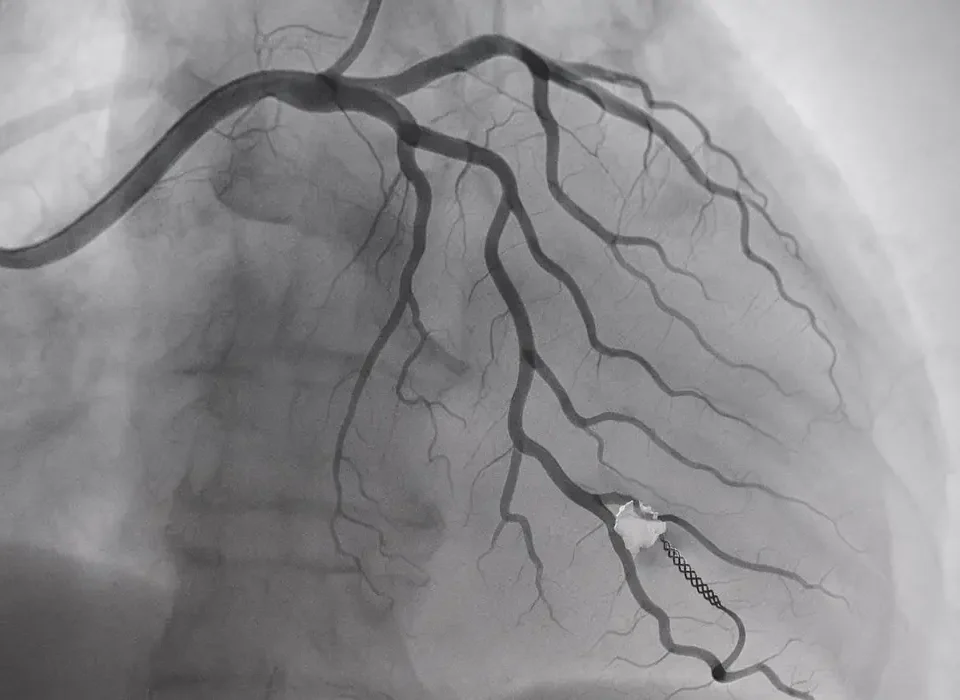

مقدمة رأب الوعاء (Angioplasty) هو إجراء طبي يستخدم لعلاج انسداد الشرايين واستعادة تدفق الدم الطبيعي إلى القلب أو أجزاء أخرى من الجسم. يعتبر هذا الإجراء طفرة في عالم طب القلب والأوعية الدموية، حيث يوفر بديلاً أقل تدخلاً مقارنة بالجراحات التقليدية. في هذا المقال، سنتناول تفاصيل إجراء رأب الوعاء، فوائده، مخاطره، والتقنيات الحديثة المرتبطة به. ما هو رأب الوعاء؟ رأب الوعاء هو إجراء غير جراحي يتم باستخدام قسطرة بالونية صغيرة تُدخل […]